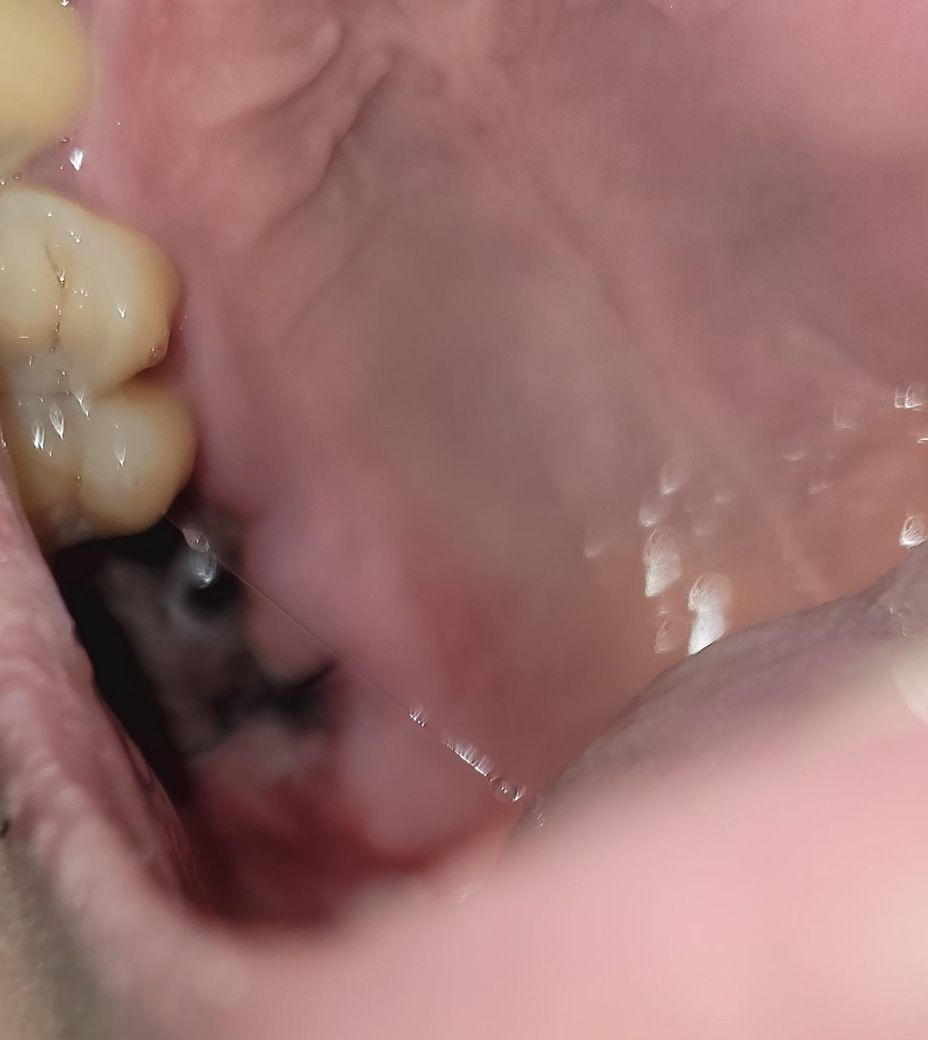

오른쪽 어금니 발치 후 피떡(혈병)이 잘 생성중 인가요?

치성 부비동염으로 인해 오른쪽 어금니 2개 발치하고

꿰멘지 3일차구요. 발치 후 구멍이 뚫려서 꿰멤

피떡이 잘 생성 되어 있는지 궁금합니다 (사진첨부)

• 2번 째 사진

피떡(혈병)은 원래 발치 후 1~2일차에 흡수되어 안보입니다. 현재 사진상으론 별다른 치유에 표면상으론 문제는 없어보입니다.

사진상을ㅇ 보면 발치한곳 잇몸이 잘 아물고 잇는거 같습니다. 자극만 가지 않도록 해주시면될것같습니다.